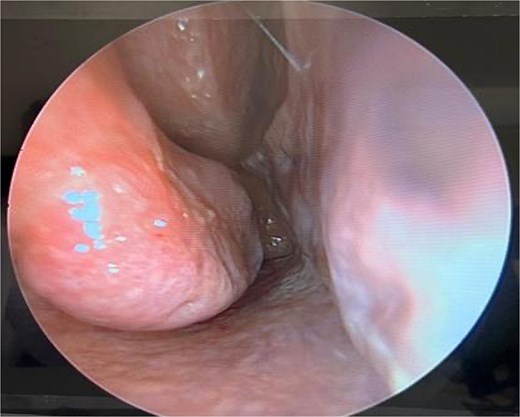

Post-operative care includes saline nasal sprays and head elevation. Patients are typically followed up at 1 week, 1 month, and 6 months postoperatively to assess healing and functional outcomes (Fig. 4).

Six-month postoperative follow-up endoscopic view demonstrating healed mucosa and patent nasal airway.